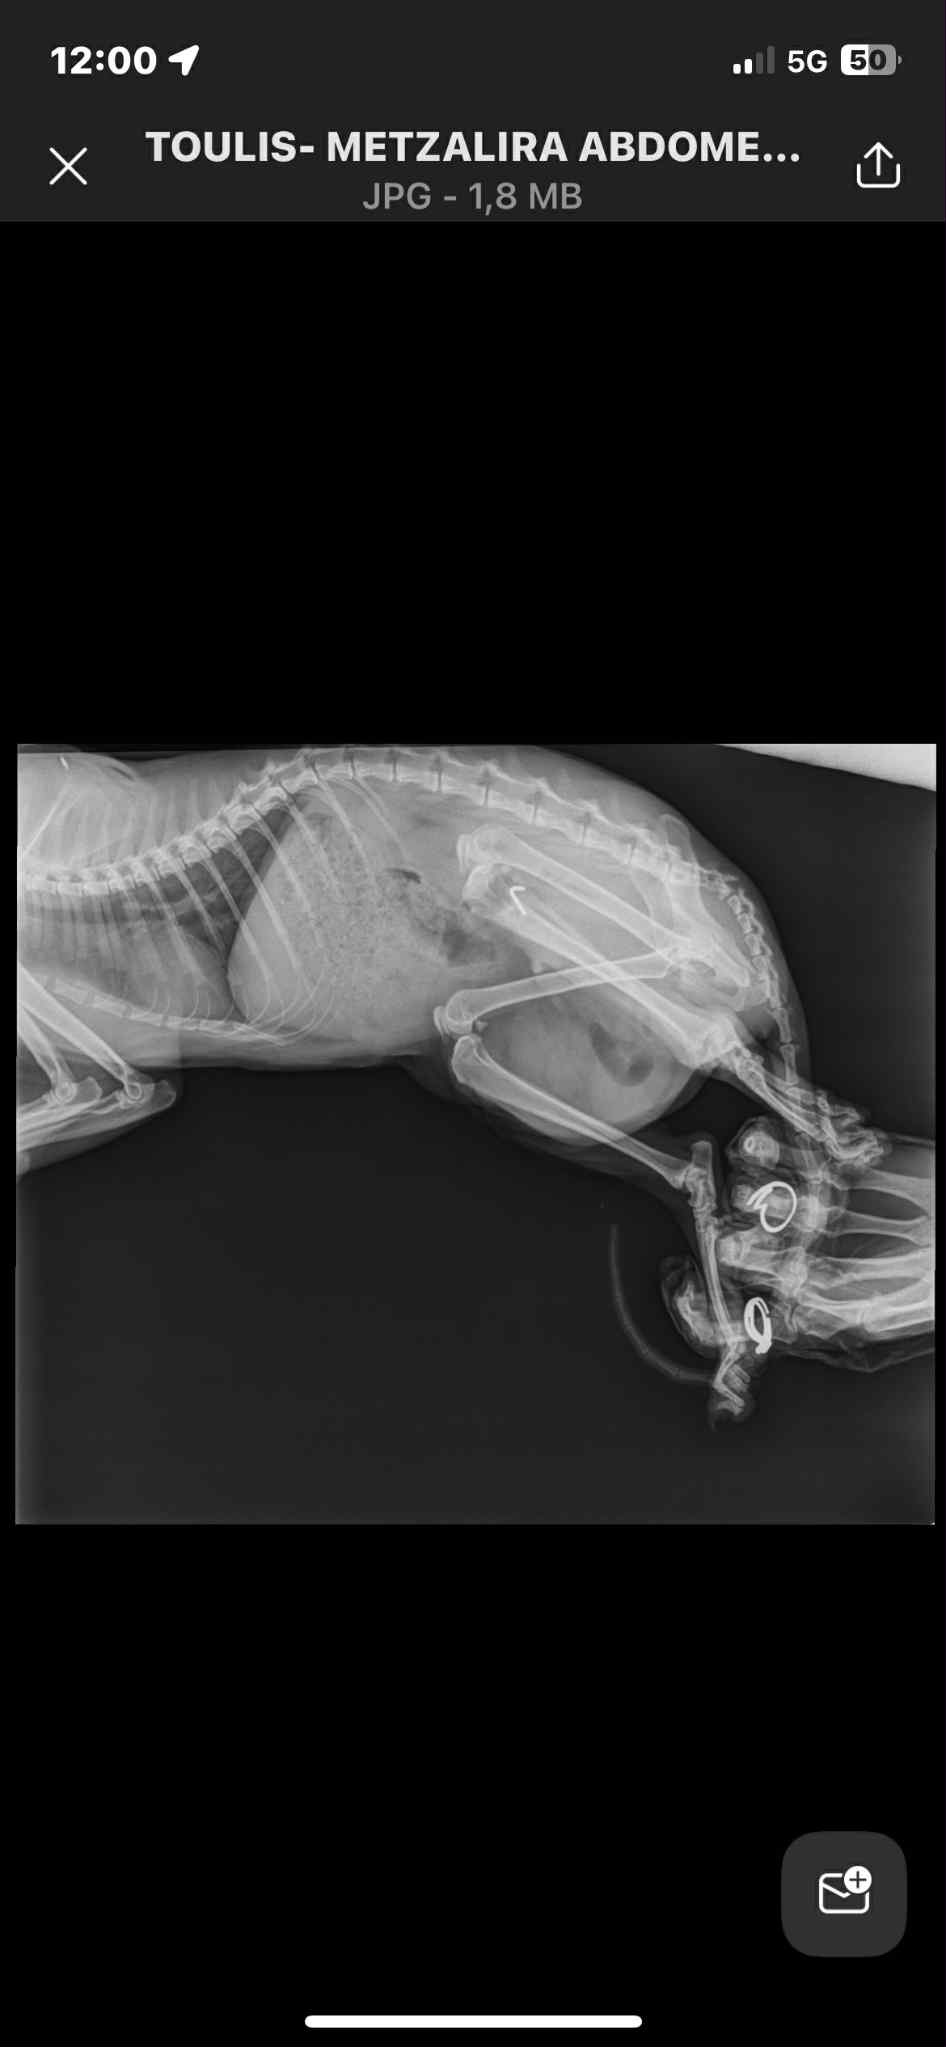

In August this year he was hit by a car and then rushed to mainland Greece for emergency surgery. He miraculously survived and has metal plates in his legs. Unfortunately this will have to stay as his bones in the legs are sadly destroyed.

My family and I heard about his dreadful story and immediately wanted to adopt him and give him a chance of a better life off the streets. During his time at the vets they performed an x ray and sadly found a lump which has been confirmed to be a hernia.